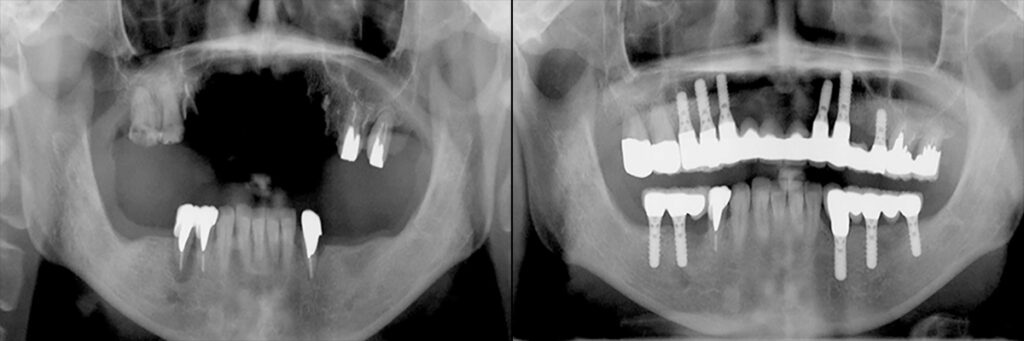

下は保存不能歯を逐次インプラントに置き換え、仮修復をしながら約2年で最終的に全歯列の修復になったもの。 貴金属の内冠を利用。 鋳造誤差やポーセレン焼き付けによる収縮を補正する最後方歯のフレームは完成時にカット。 治療完了後18年経過